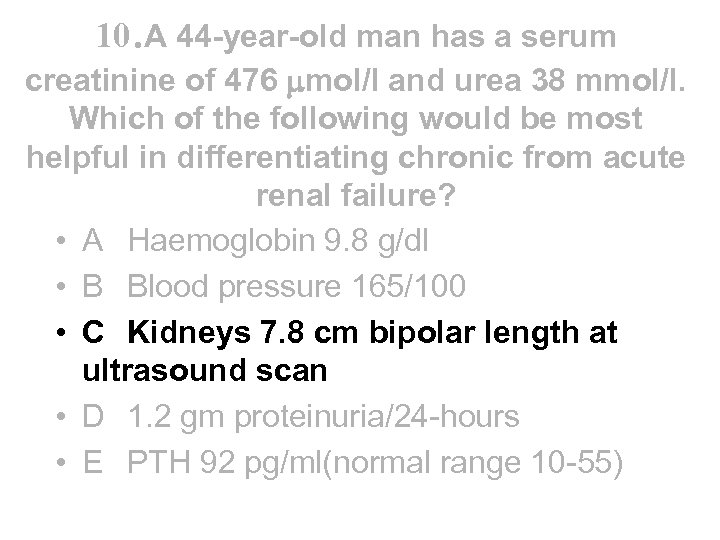

10. A 44 -year-old man has a serum creatinine of 476 mol/l and urea 38 mmol/l. Which of the following would be most helpful in differentiating chronic from acute renal failure? • A Haemoglobin 9. 8 g/dl • B Blood pressure 165/100 • C Kidneys 7. 8 cm bipolar length at ultrasound scan • D 1. 2 gm proteinuria/24 -hours • E PTH 92 pg/ml(normal range 10 -55)

10. A 44 -year-old man has a serum creatinine of 476 mol/l and urea 38 mmol/l. Which of the following would be most helpful in differentiating chronic from acute renal failure? • A Haemoglobin 9. 8 g/dl • B Blood pressure 165/100 • C Kidneys 7. 8 cm bipolar length at ultrasound scan • D 1. 2 gm proteinuria/24 -hours • E PTH 92 pg/ml(normal range 10 -55)

10. A 44 -year-old man has a serum creatinine of 476 mol/l and urea 38 mmol/l. Which of the following would be most helpful in differentiating chronic from acute renal failure? • A Haemoglobin 9. 8 g/dl • B Blood pressure 165/100 • C Kidneys 7. 8 cm bipolar length at ultrasound scan • D 1. 2 gm proteinuria/24 -hours • E PTH 92 pg/ml(normal range 10 -55)

10. A 44 -year-old man has a serum creatinine of 476 mol/l and urea 38 mmol/l. Which of the following would be most helpful in differentiating chronic from acute renal failure? • A Haemoglobin 9. 8 g/dl • B Blood pressure 165/100 • C Kidneys 7. 8 cm bipolar length at ultrasound scan • D 1. 2 gm proteinuria/24 -hours • E PTH 92 pg/ml(normal range 10 -55)

Chronic v acute renal failure • Chronic Haemoglobin Blood pressure Renal size Proteinuria Calcium and PO 4 PTH • Acute • usually anaemic but not ADPKD • HT if glomerular • usually small* • none to heavy if glomerular • usually low Ca with high PO 4 • variable - high in 2 y hyperpara • may become anaemic quickly • HT if RPGN • normal • none to heavy if RPGN • usually low Ca with high PO 4 • variable - can be high *Normal kidney length >10 cms on sonar, borderline 9 -10 cms, small <9 cms, unequal if >1. 5 cms difference, but patients with CRF can have normal size kidneys

Chronic v acute renal failure • Chronic Haemoglobin Blood pressure Renal size Proteinuria Calcium and PO 4 PTH • Acute • usually anaemic but not ADPKD • HT if glomerular • usually small* • none to heavy if glomerular • usually low Ca with high PO 4 • variable - high in 2 y hyperpara • may become anaemic quickly • HT if RPGN • normal • none to heavy if RPGN • usually low Ca with high PO 4 • variable - can be high *Normal kidney length >10 cms on sonar, borderline 9 -10 cms, small <9 cms, unequal if >1. 5 cms difference, but patients with CRF can have normal size kidneys